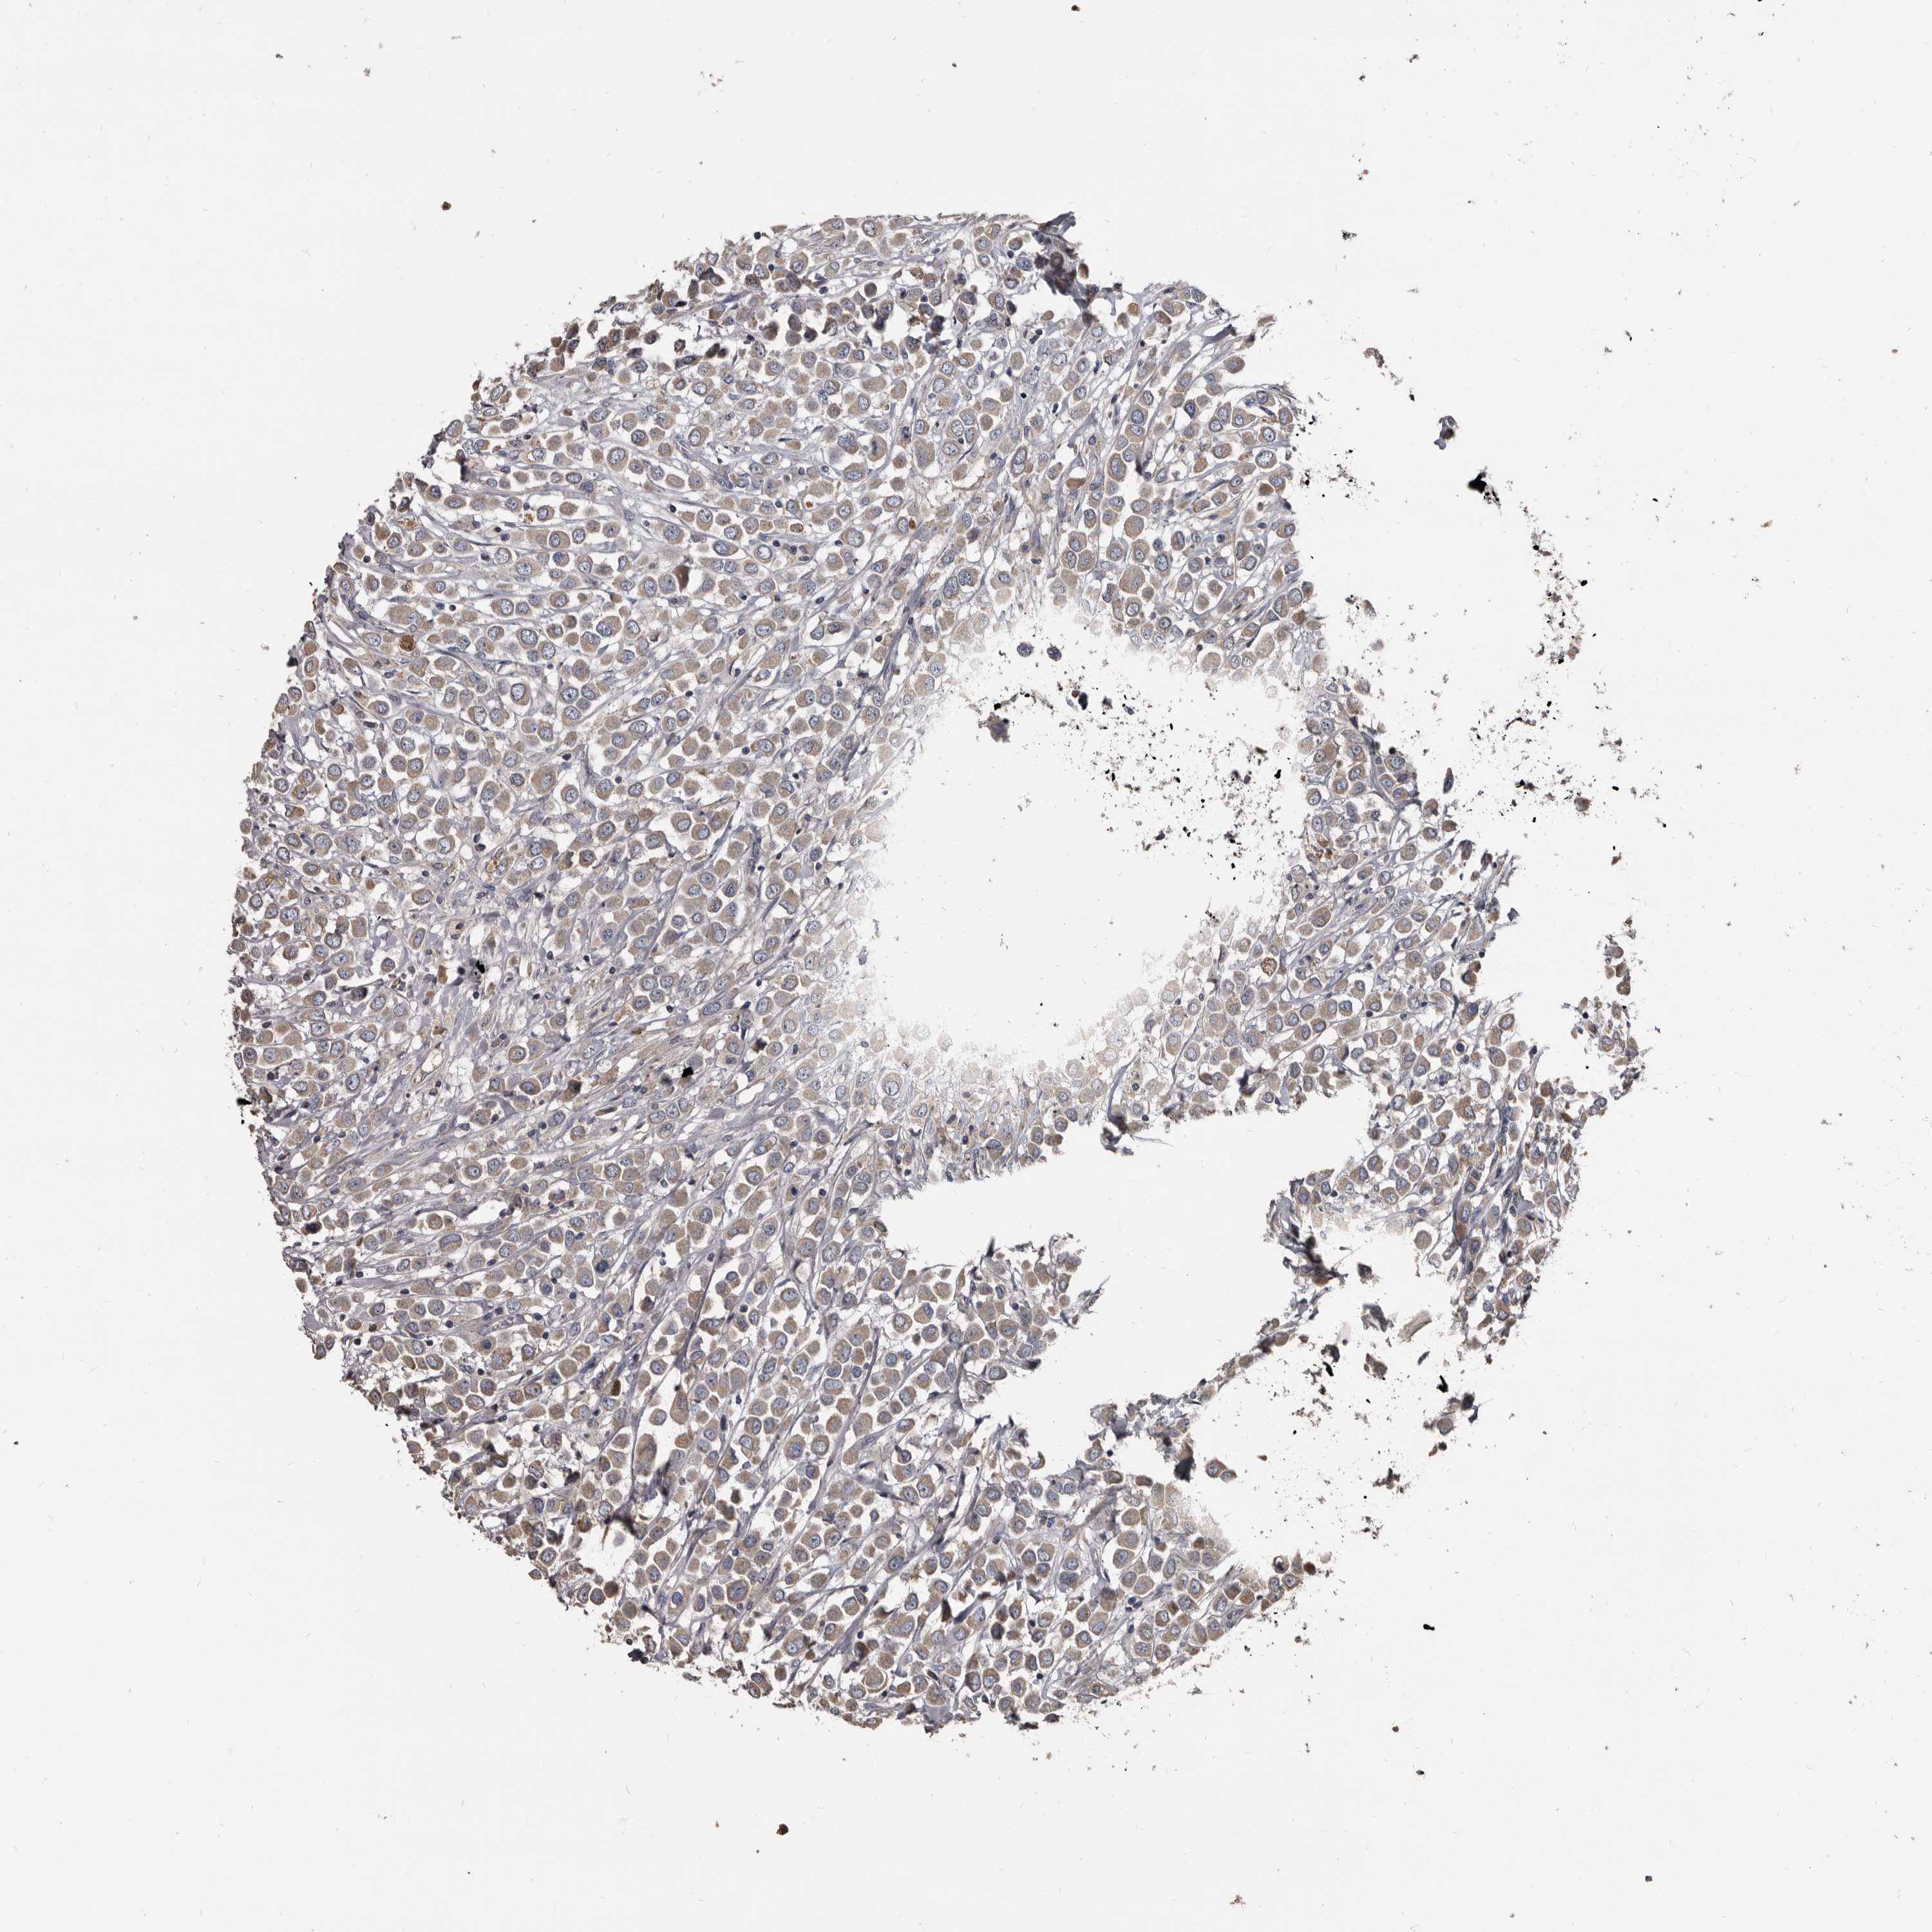

CANCER BREAST CANCER Show tissue menu

BRCA TCGA BRCA VALIDATION PROTEIN EXPRESSION

ANTIBODIES

AND

VALIDATION